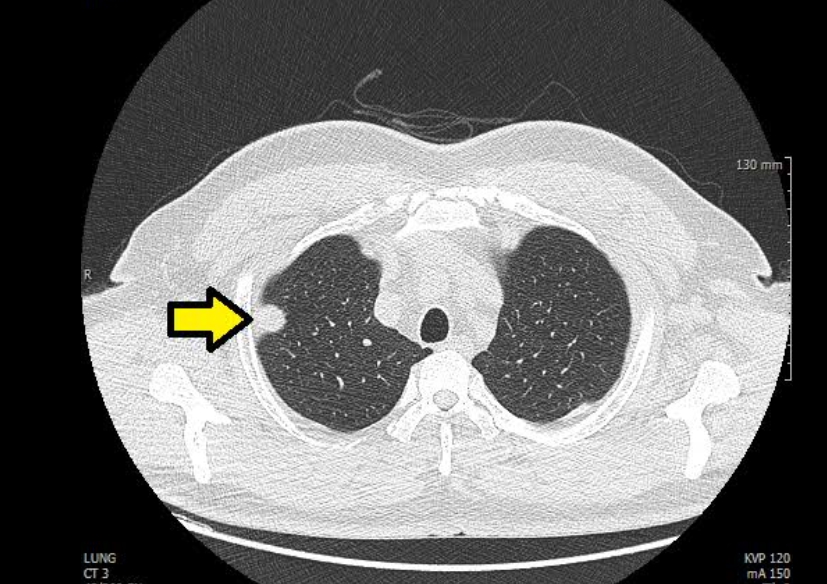

Q8. 흉부CT 결과에서 ‘폐결절’이 나왔다는 말은 뭔가요?

A. 흉부ct로 볼수있는 질환 폐결절은 말 그대로 폐 안에 작은 혹이 있다는 뜻입니다. 대부분 양성(암이 아님)이고, 오래된 염증이나 석회화에 의한 것일 수도 있습니다. 그러나 결절의 크기가 8mm 이상이거나, 형태가 불규칙한 경우에는 추가 검사가 필요합니다. 영상의학과에서는 결절의 밀도, 경계, 주변 변화 등을 세밀하게 분석해 암 가능성을 판단합니다.